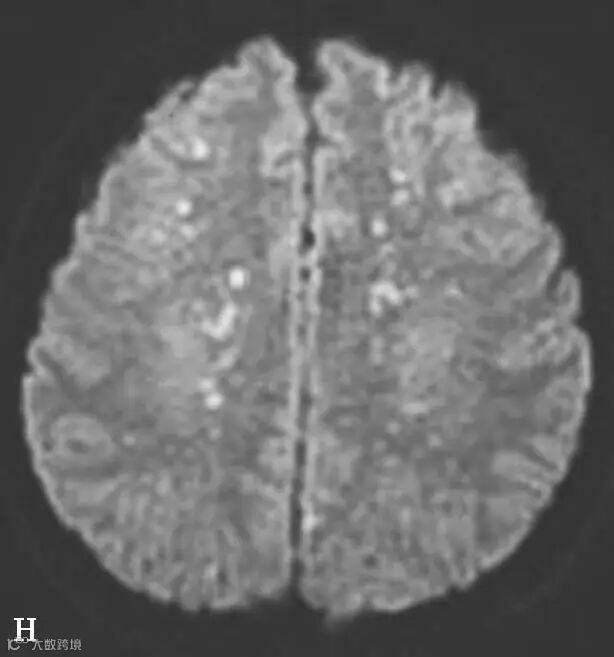

图6-11-2 弥漫性轴索损伤

男,36岁,外伤后2天。A~J(A、B.T2WI,C、D.T1WI,E、F.T2WI-FLAIR,G、H.DWI,I、J.ADC图):双侧额叶、半卵圆中心及胼胝体压部可见多发斑点状等T1稍长T2信号,边缘不清,FLAIR及DWI呈高信号,ADC图病灶信号减低 。